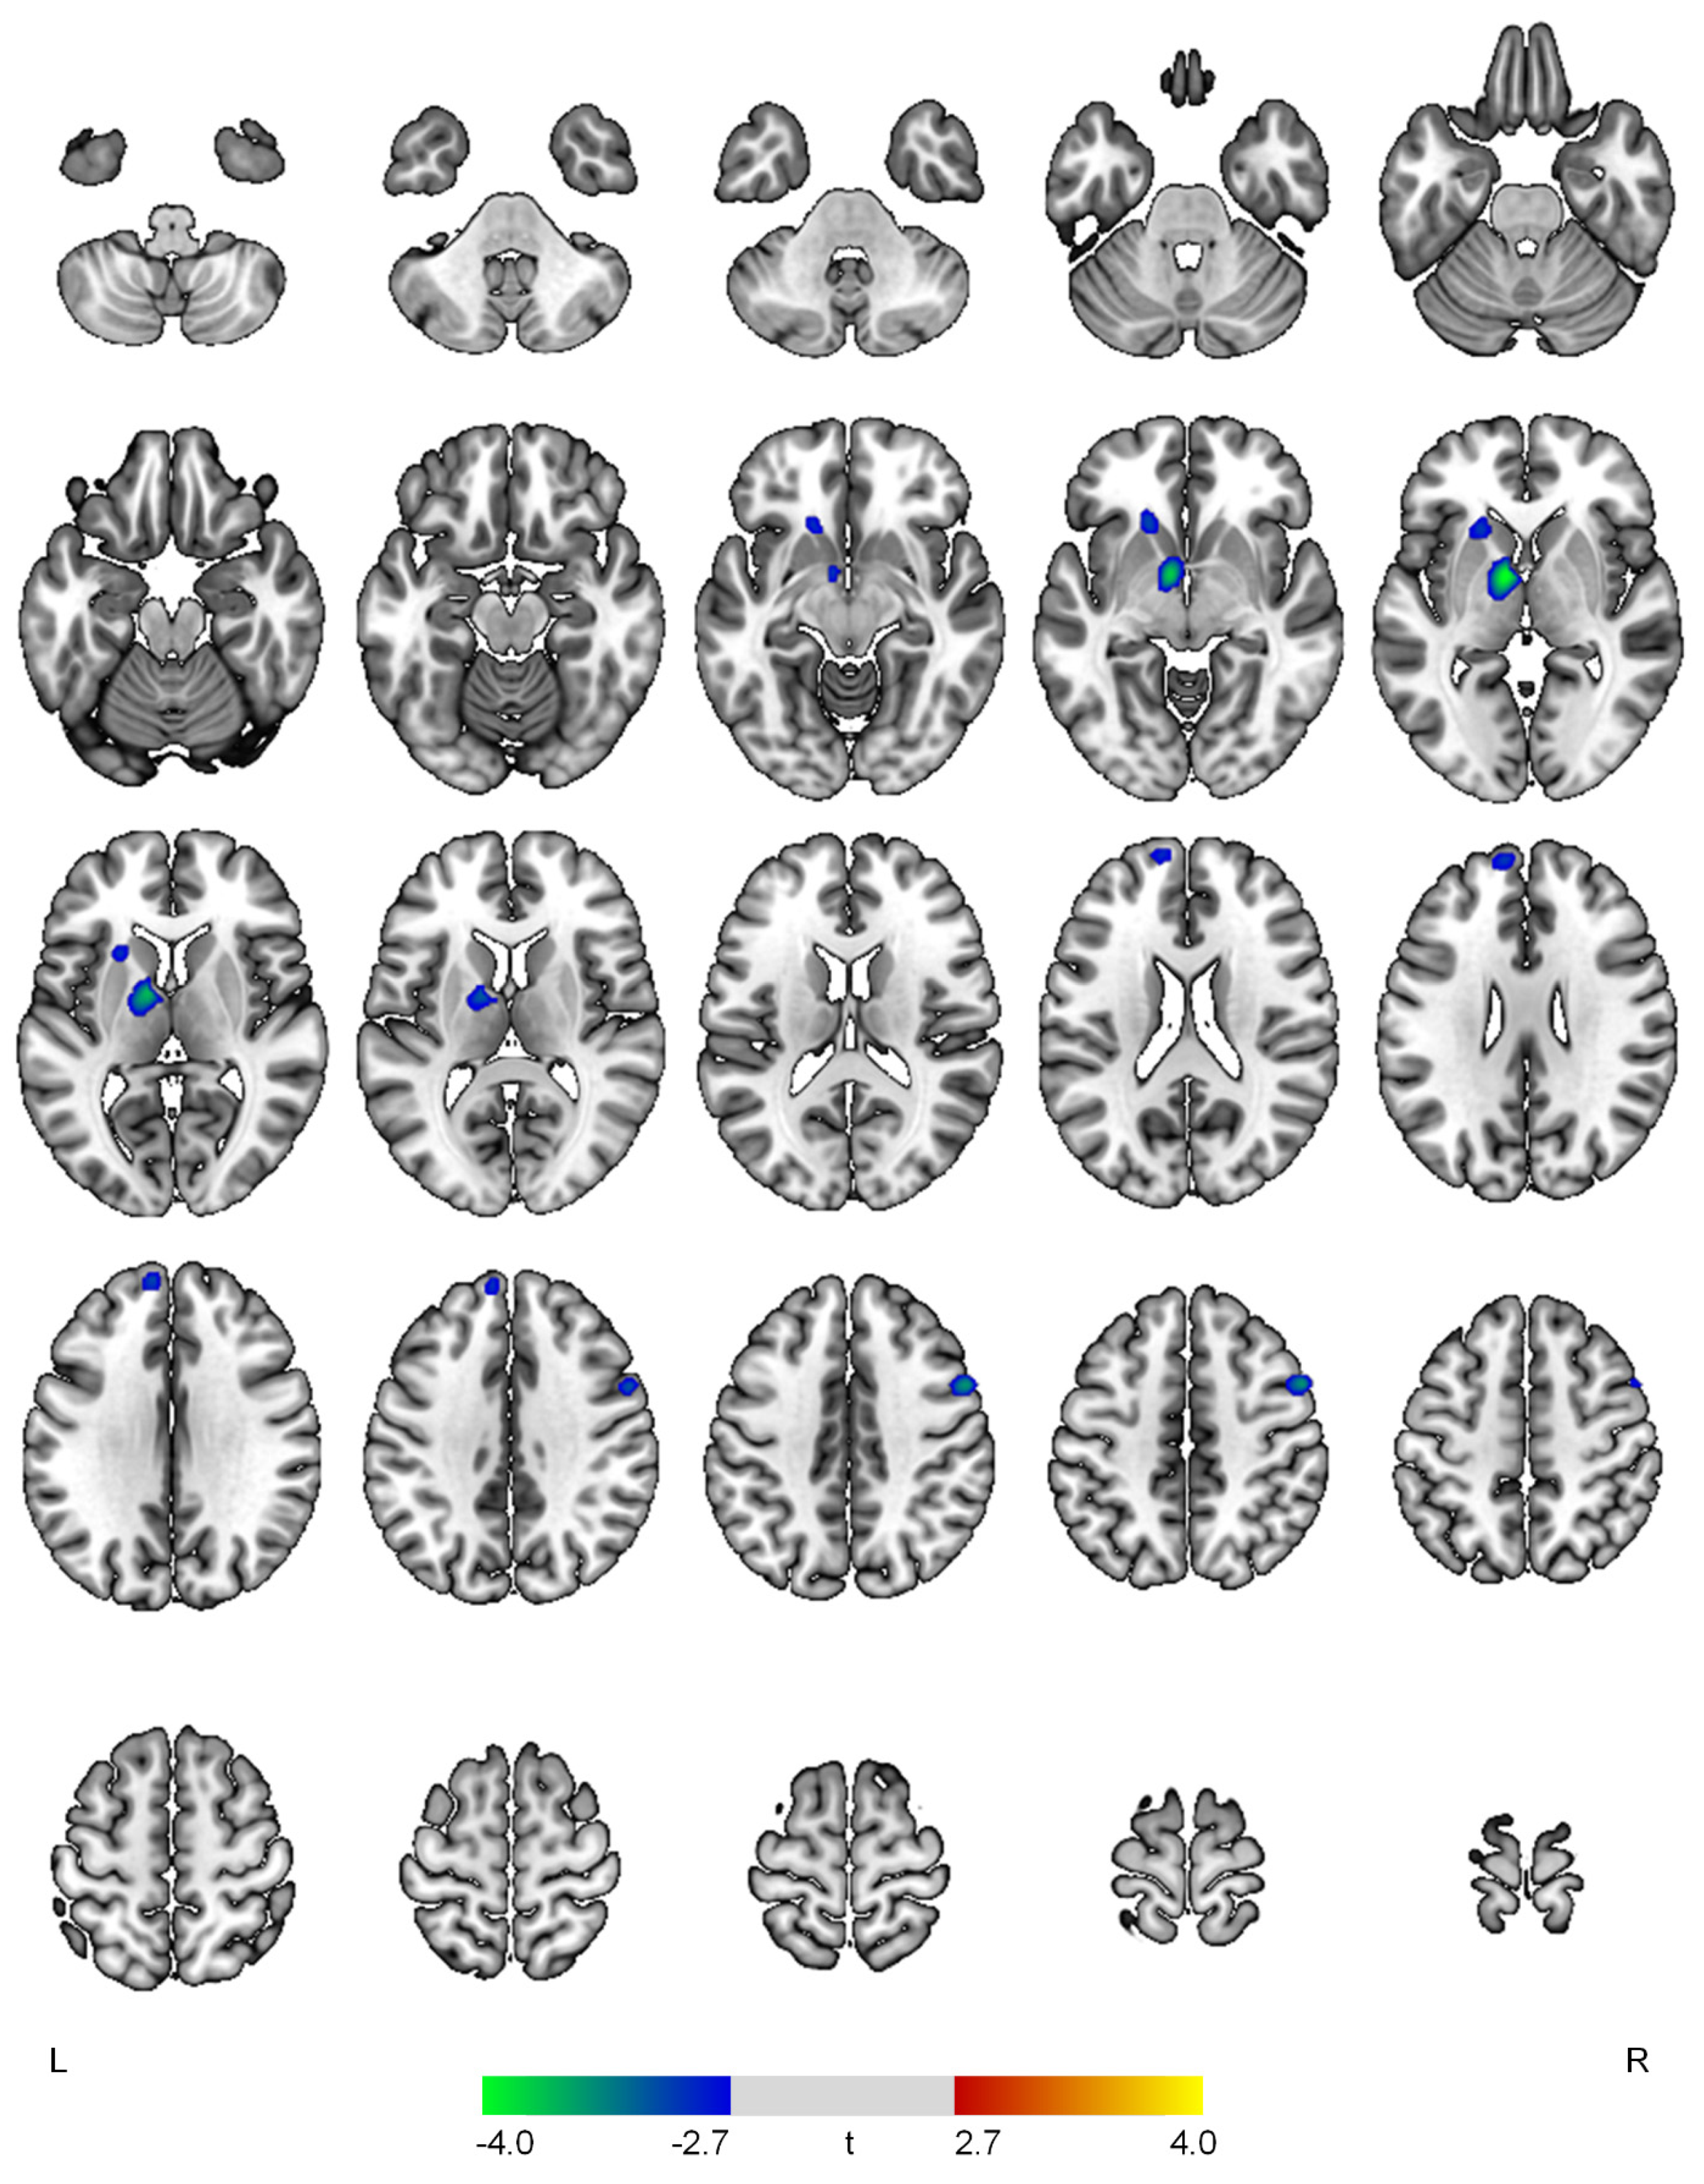

Results of the SPECT image analysis are presented in Table 2 and Figure 1, Figure 2, Figure 3 and Figure 4. The affective domain scores showed negative correlations with rCBF in the left thalamus (t = 4.08, p < 0.001), right precentral gyrus (t = 3.59, p < 0.001), left superior frontal gyrus (t = 3.06, p = 0.002), and left caudate (t = 3.05, p = 0.002) (Figure 1).

Figure 1.

Positive (red-yellow) or negative (blue-green) correlations between regional cerebral blood flow and the affective domain in patients with early Alzheimer’s disease. The color bar represents t values at each voxel. L—left; R—right.

The affective domain showed negative correlations with rCBF in the superior frontal and precentral gyri, thalamus, and caudate. Previous studies have provided converging evidence that dysfunction and atrophy of the cortico-striatal-pallidal-thalamic circuits may, in part, account for the pathophysiology of major depressive disorder (MDD) [16]. This circuit consists of the prefrontal cortex, anterior cingulate cortex, basal ganglia, and thalamus and supports diverse emotional, cognitive, and motor processes. The superior frontal gyrus is considered as a core brain region for emotional processing and modulation such as rumination and cognitive control over negative feelings [17]. In AD patients with depressive or anxiety symptoms, reduced rCBF and hypometabolism of the superior frontal gyrus have been consistently reported [7,8]. The precentral gyrus is known to receive projections from the basal ganglia [18]. The abnormalities in the frontal and basal ganglia circuits may lead to psychomotor retardation and impaired action planning, which are commonly found in MDD [18]. A previous resting-state functional magnetic resonance imaging (rs-fMRI) study reported reduced regional homogeneity in both the superior frontal and precentral gyri in AD patients with depressive symptoms [19]. Deficits of the caudate may lead to psychomotor retardation and decreased hedonic drive, which are likely to be mediated by dopaminergic dysfunction [20]. A graph theoretical analysis of rs-fMRI data in AD demonstrated an inverse correlation between the affective domain scores and the closeness centrality of the caudate [13]. In addition, individuals with both AD and late-onset depression showed gray matter hypodensity in the caudate nucleus [21].